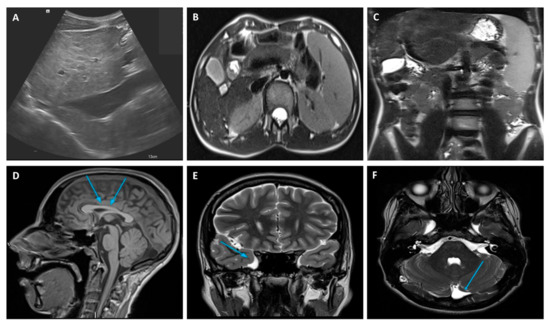

An extensive diagnostic work-up of CLD was performed with laboratory, radiological, and clinical investigations, which finally ruled out the most frequent and known causes of CLD at that age. LFTs were particularly unremarkable with no abnormal values of cholestasis, liver enzymes, tumor markers, and hepatic synthetic function. A full blood count revealed mild thrombocytopenia due to hypersplenism secondary to the enlarged spleen size. An abdominal doppler ultrasound scan and magnetic resonance imaging (MRI) confirmed the chronic liver involvement, showing hepatic parenchymal micro- and macronodular transformation, as well as splenomegaly (Figure 1). Upper gastro-intestinal endoscopy ruled out esophageal varices but showed mild portal hypertension (PH)-related gastropathy. In addition, we performed echocardiography and ophthalmology reviews, which were both normal, while a psychological evaluation was performed, revealing a non-verbal IQ of 63 (which was in keeping with mild disability) through the Raven matrices.

A liver biopsy was then performed to further investigate CLD etiology. Histology revealed micro- and macronodular cirrhosis characterized by disturbed architecture due to the presence of veno-venous fibrotic septa that delimited parenchymal nodules (Figure 2). A slight inflammatory lymphomonocyte infiltrate was present in the septa and in the portal spaces. Close to an anatomical septum, a cluster of optically empty cells intermixed with atrophic hepatocytes was present (Figure 3). These cells, found with immunohistochemical analysis, were hepatocyte paraffin 1 (HepPar1)-, smooth muscle actine (SMA)+, desmin-, glial fibrillary acidic protein (GFAP)-, and S100-, and they were consistent with Ito perisinusoidal cells (PSCs) in a setting of s.c. spongiotic pericytoma. The absence of a conclusive liver diagnosis and multiorgan involvement, suggestive of a genetic syndrome, made it mandatory to perform a genetic test; this was at first examined with a targeted liver genes panel (Figure S1) and then expanded to whole-exome sequencing (WES). The genetic test showed a heterozygous de novo frameshift variant c.5751_5754delAGTT in the SON gene. This variant is classified as pathogenetic (class 5), according to ACMG guidelines (Figure 4), and is already reported in the medical literature [9]. The finding of the SON mutation was unexpected from a hepatology point of view, advocating an overall patient phenotype reassessment, which was ultimately found to be highly compatible with ZTTK syndrome, according to the literature (Table 1) [2,3,9,10,11,12,13,14,15,16,17]. To further investigate the possible link with ZTTK syndrome, a brain MRI was performed, and its findings were highly similar to previous descriptions (Figure 1).

Figure 1. Liver doppler ultrasound (A) and abdominal MRI (B) findings showing hepatic parenchymal micro- and macronodular transformation with associated splenomegaly (C). MRI brain abnormalities: (D) mild hypoplasia of the rostrum and splenium of the corpus callosum, (E) temporo-polar arachnoid cyst, (F) retro-infero-cerebellar arachnoid cyst. MRI, Magnetic Resonance Imaging.